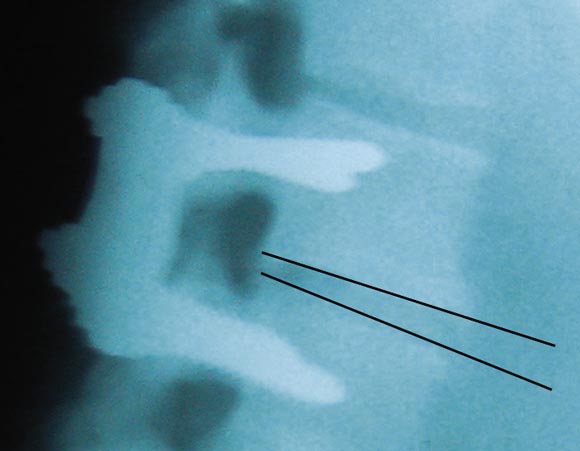

The second patient's bone had an abnormal histological appearance, and, despite an omnivorous diet, her choice to avoid direct sunlight for many years had resulted in profound vitamin D deficiency.